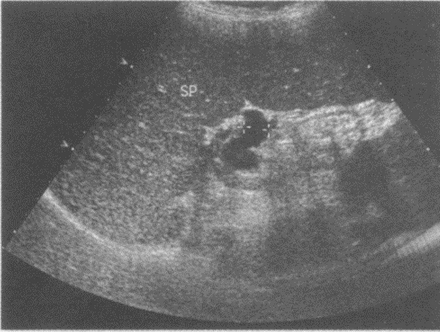

临床资料:男,50岁,自述患乙型肝炎20年,诊断肝硬化门静脉高压8年余。超声综合描述:脾厚6.8cm,脾长径17.9cm,肋下5.1cm,脾静脉1.2cm,脾回声粗糙不均匀。

超声提示()

A:脾动脉增宽

B:脾大脾静脉增宽

C:脾厚

D:食道胃底静脉曲张